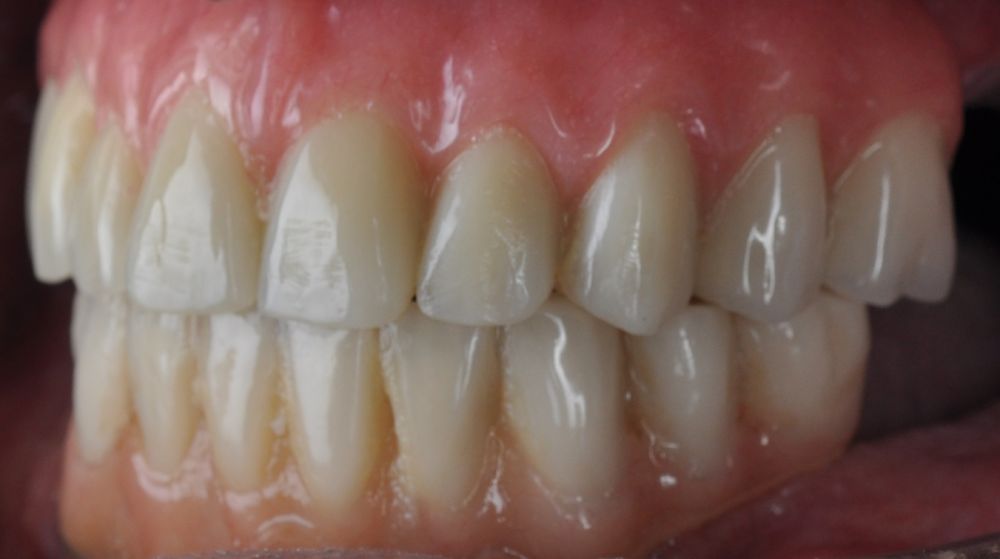

Clinical Case: A subperiosteal sintered titanium structure was fabricated with six transepithelial connections that were rehabilitated with an immediate implant supported fixed prosthesis made of PMMA. Two months later, a sintered chromium-cobalt framework with machined bases covered with acrylic resin teeth was fabricated as the final restoration. At one year follow-up, the case remains stable.